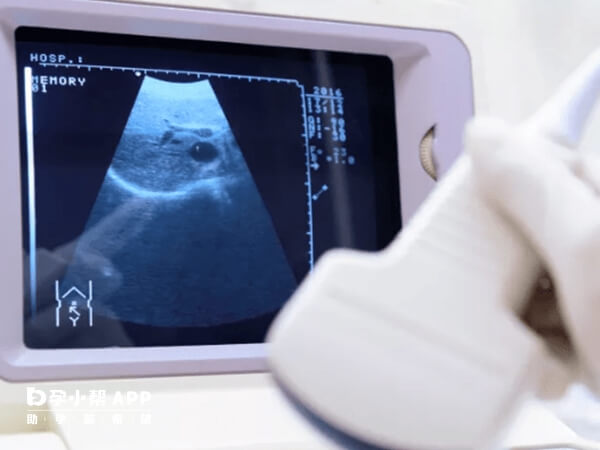

通常情況下,女性在試管移植成功後,需要做三次B超來確定胚胎的發育情況,術後45天一般是做二超,是為了檢查胚胎有無胎心胎芽,確認單胎、二胎甚至三胎情況,一般來說,做試管嬰兒出現無胎心胎芽的概率較小,如果此時檢測出胚胎無胎心胎芽,那胎停育的機率很高,有的能達到90%,建議女性這種情況下要及時的去醫院檢查孕酮,以及血HCG值,如果孕酮值正常,可在一週後去醫院複查胚胎胎心胎芽情況。

一般來說,試管移植後女性成功懷孕,孕6周時就會出現胎心胎芽,哪怕胚胎生長髮育較為緩慢,也應該在術後35-45天中正常出現胎心胎芽。因此女性在胚胎移植後的45天,檢測時胚胎無胎心胎芽停育的機率有以下情況: